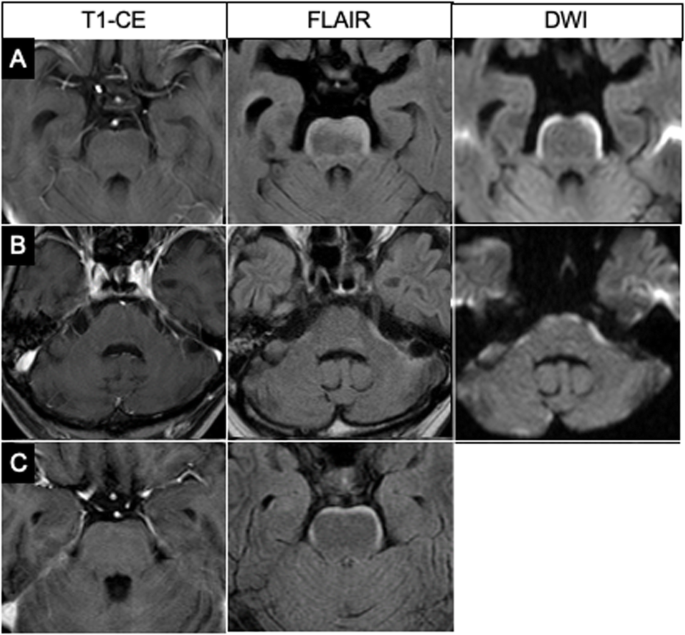

FLAIR images showed a hyperintense band along the anterior and lateral surfaces of the brainstem extending to the cerebellar peduncle, even to the walls of the fourth ventricle. It was a clear and dense layer on the surface of the brainstem looking like a bloomy rind on cheese, symmetrical in all 11 cases, and had some accentuation or interruption (Fig. 2). Overall, 6 of the 11 cases (54.5%) showed no abnormal enhancement of the brainstem, but five had only subtle enhancement on part of the lesion on GdCE MR images. Diffusion-weighted (DW) imaging was performed for 7 of the 11 patients and demonstrated the surface lesions as having restricted diffusion in 3 patients and normal in 4 of them (Table 1).

Three representative cases of bloomy rind sign. Although no abnormalities are seen on the brainstem on GdCE T1-weighted images, FLAIR images show hyperintensity along the brainstem surface in all three cases. Figure 2a and c show FLAIR hyperintensity on the antero-lateral surface of the pons, and Fig. 2b shows it along the antero-lateral cerebellar peduncle. DW images show restricted diffusion at the same lesions of two patients. DW images are not available for the third patient. Two patients (Figs. a and c) had positive CSF cytology, but one (Fig. b) did not undergo CSF examination because of neurological signs and restricted enhancement in the internal acoustic canals on GdCE images